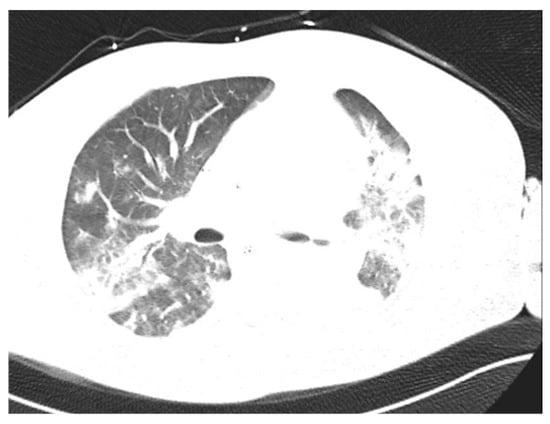

| 11 | 35/M | Pneumonia ARDS | none | Rhinovirus/Enterovirus (PN+) c | 21 | 15 | yes | 19 days | Transferred to the transplant center |

| 11 | Septex ECMO c | no | sputum + (PN+) d | Ertapenem Linezolid | Ertapenem Linezolid Penicillin |